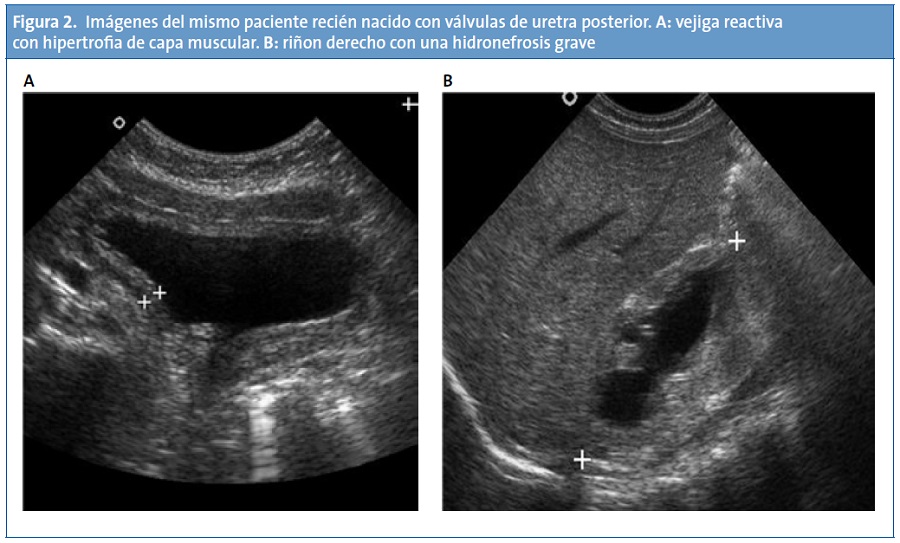

La realidad asistencial pediátrica actual, digamos “no oficial”, es otra bien distinta, pues la técnica ya está siendo utilizada a diario por pediatras españoles. El ejemplo más claro es la subespecialidad de Cardiología Pediátrica, en la que resulta imprescindible. En los servicios pediátricos, las diferentes subespecialidades hacen uso de la ecografía: los neuropediatras o neonatólogos realizan ecografías cerebrales transfontanelares en neonatos y lactantes (Fig. 1). Los intensivistas pediátricos y neonatales acceden a vías centrales guiados por ecografía7-8, o para documentar un neumotórax9 o asegurar la intubación traqueal para distinguirla de la esofágica10. Los gastroenterólogos pediátricos realizan ecografías abdominales donde valoran el hígado, el bazo o cuantifican el reflujo gastroesofágico, e incluso realizan seguimiento en postrasplantados hepáticos para observar signos de rechazo. No son pocos los neonatólogos que realizan ecocardiografías “furtivas” en las guardias ante pacientes inestables para el diagnóstico de válvulas de uretra posterior (Fig. 2) o para descartar una cardiopatía cuando no tienen un cardiólogo pediátrico a su disposición. Los médicos de Urgencias Pediátricas se forman cada vez más mediante cursos llamados Eco-FAST11, que permiten diagnósticos en Urgencias ante pacientes politraumatizados para detectar líquido libre en el abdomen, ascitis, neumotórax o una pericarditis. Todos estos son unos pocos ejemplos de lo que hoy en día realizan los pediatras, a diario, con un beneficio importante de los pacientes, ya que en muchos casos es necesario obtener información inmediata y existen limitaciones como que el radiólogo no está presente o disponible, o que la técnica se realiza en un momento diferido, en el que ya no nos proporciona información o incluso que el radiólogo no tenga experiencia en población pediátrica por poner algunos ejemplos. Se han publicado recientemente resultados de trabajos de ecografía realizada por pediatras de Atención Primaria12, lo que muestra que, si bien no es una realidad todavía extendida, la ecografía para los clínicos comienza su andadura en España.

Todas las imágenes han sido realizadas por pediatras durante una guardia.